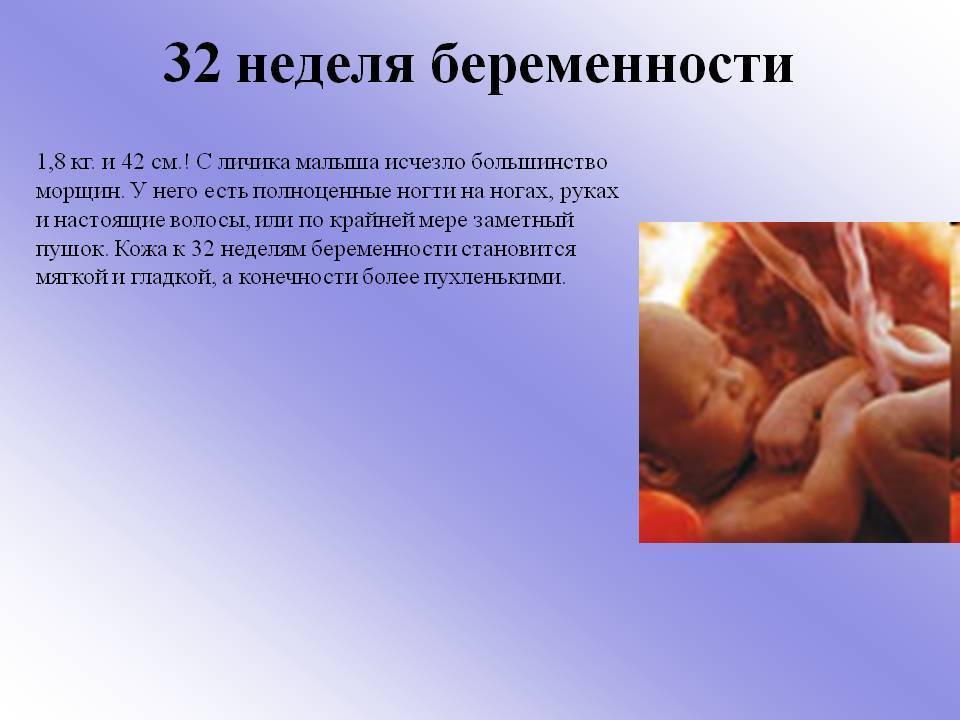

Развитие плода на 31 неделе беременности